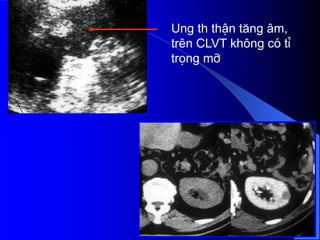

- Siãu ámphán biãût âæåüc khäúi âàûc vaì dëch. Nãúu laì khäúi âàûc seî xem xeït cáúu truïc ám, coï thãø giaím, âäöng hoàûc tàng ám, xem âäü âäöng nháút ám, väi hoïa. Nãúu laì khäúi dëch, seî tçm täø chæïc âàûc hoàûc vaïch trong nang. Siãu ám coï thãø tháúy haûch di càn, xám láún ténh maûch. Noïi chung khi phaït hiãûn khäúi âàûc trãn siãu ám, cáön chuûp CLVT âãø âaïnh giaï roî hån baín cháút, sæû xám láún, di càn.

- CLVT phánbiãût khäúi âàûc hay dëch, phaït hiãûn väi hoïa nhoí, xuáút huyãút trong u, tçnh traûng tæåïi maïu cuía u. Pháön låïn træåìng håüp phán biãût âæåüc u laình vaì u aïc. Xem xeït âæåìng dáùn niãûu bë giaîn, bë xám láún. CLVT kiãøm tra di càn haûch xám láún vuìng xung quanh, xám láún maûch maïu, di càn xa, cå såí âãø phán giai âoaûn tiãún triãøn u, cáön thiãút cho phæång phaïp âiãöu trë.

Ung th thËnt¨ng ©m, trªn CLVT kh«ng cã tØ träng mì